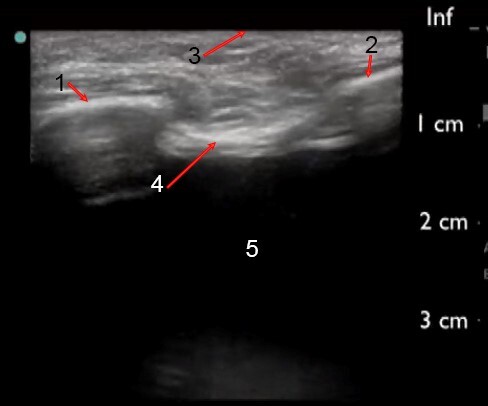

胸腔穿刺术线性胸腔积液超声图像

头侧肋骨

尾侧肋骨

胸壁

胸膜壁层

胸腔积液